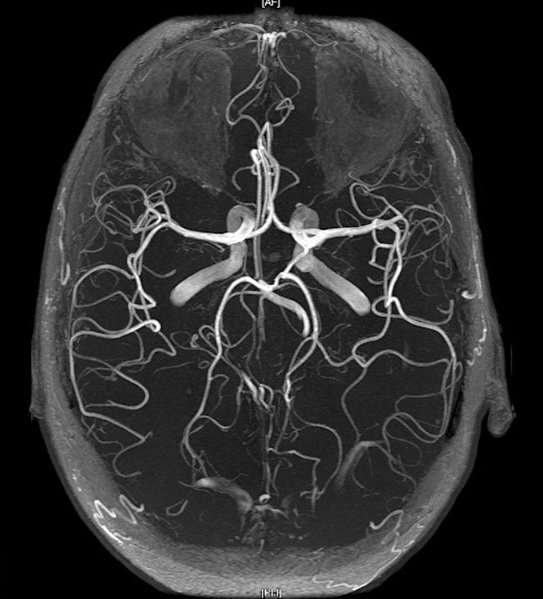

Для постановки диагноза церебрального атеросклероза необходим осмотр пациента неврологом. Диагностика заболевания базируется на данных анамнеза, клинических проявлениях, а также данных ряда дополнительных обследований. Проведение дуплексного сканирования дает возможность оценить состояние внечерепных артерий, которые питают головной мозг. Данный диагностический метод в сочетании с ультразвуковым исследованием черепных артерий позволяет получить информацию о локализации атеросклеротического поражения, степени сужения кровеносного сосуда, а также о характере атеросклеротической бляшки. Состояние кровеносных сосудов головного мозга можно оценить путем проведения ангиографического исследования. Компьютерная томография обычно применяется у пациентов с церебральным атеросклерозом, которые перенесли инсульт, для уточнения локализации поражения и выбора тактики дальнейшего лечения. Для оценки состояния церебральных сосудов также используют магниторезонансную томографию. Оценить функциональное состояние мозга можно при посредстве электроэнцефалографии. Патологические изменения сосудов сетчатки можно выявить при проведении офтальмоскопии. При нарушениях слуха требуется осмотр пациента оториноларингологом с проведением аудиометрии. Может потребоваться проведение иммунологического исследования, а также биохимического анализа крови для определения уровня холестерина и липопротеинов (липидограмма).

Подтвердить диагноз церебральный атеросклероз позволяет МРТ сосудов головного мозгаЦеребральный атеросклероз неизлечим, однако при проведении своевременной адекватной терапии возможно замедлить его прогрессирование. При лечении церебрального атеросклероза в первую очередь необходимо устранить неблагоприятные факторы, которые обусловили развитие патологического процесса.